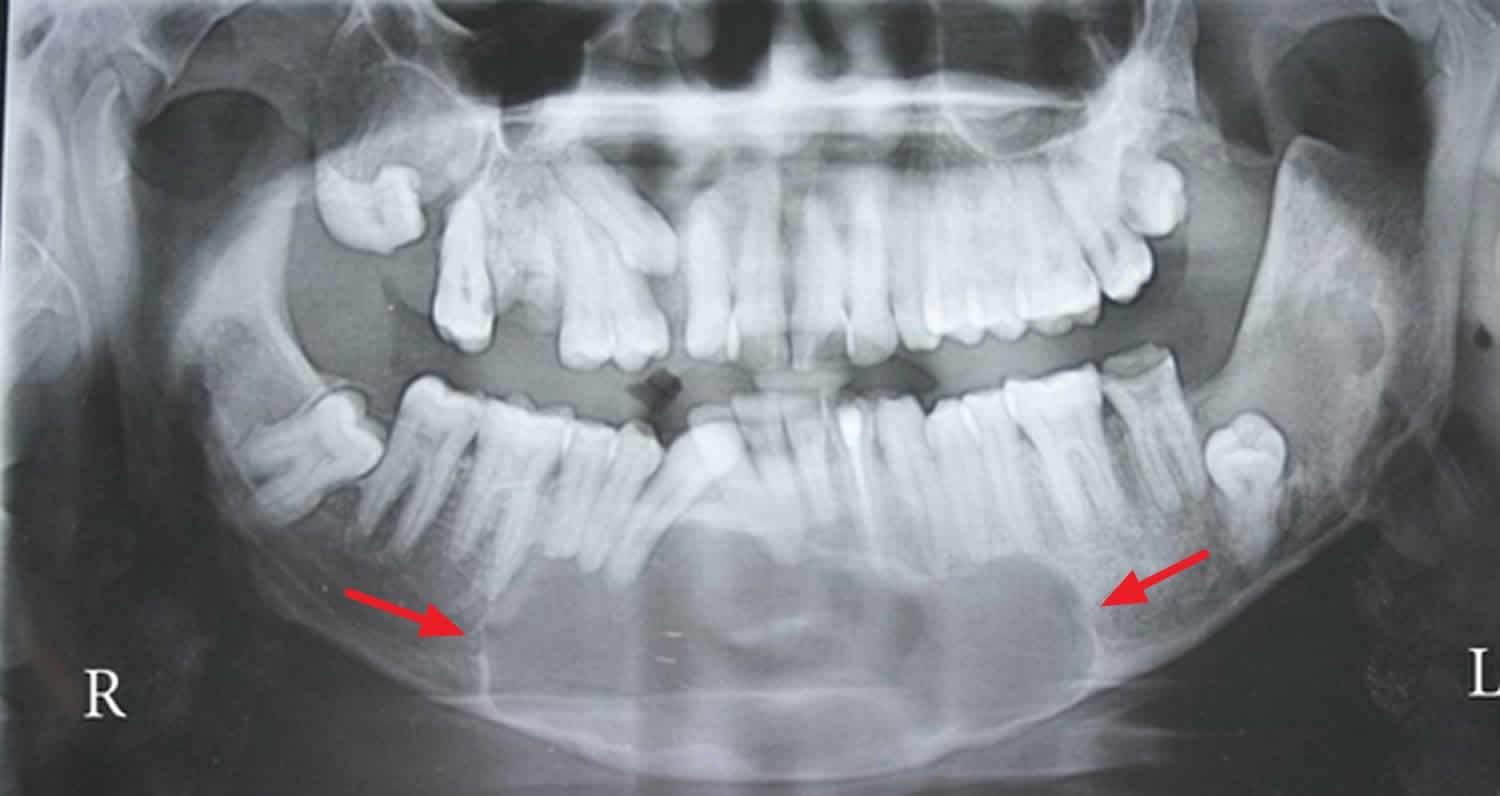

Differential diagnosis Imaging differential considerations include.

In the WHOIARC classification of head and neck pathology this clinical entity had been known for years as the odontogenic. Dentigerous cyst both dentigerous cysts and odontogenic keratocysts can be positioned pericoronally dentigerous cysts tend to attach at the cemento-enamel junction of teeth radicular cyst. Comprehensive review with recent updates on who classification 2017.

It most often affects the posterior mandible and most commonly presents in the third decade of life. Osteotomy in the trigonoretromolar region until the exposure of the lesion. Enucleation of the lesion.